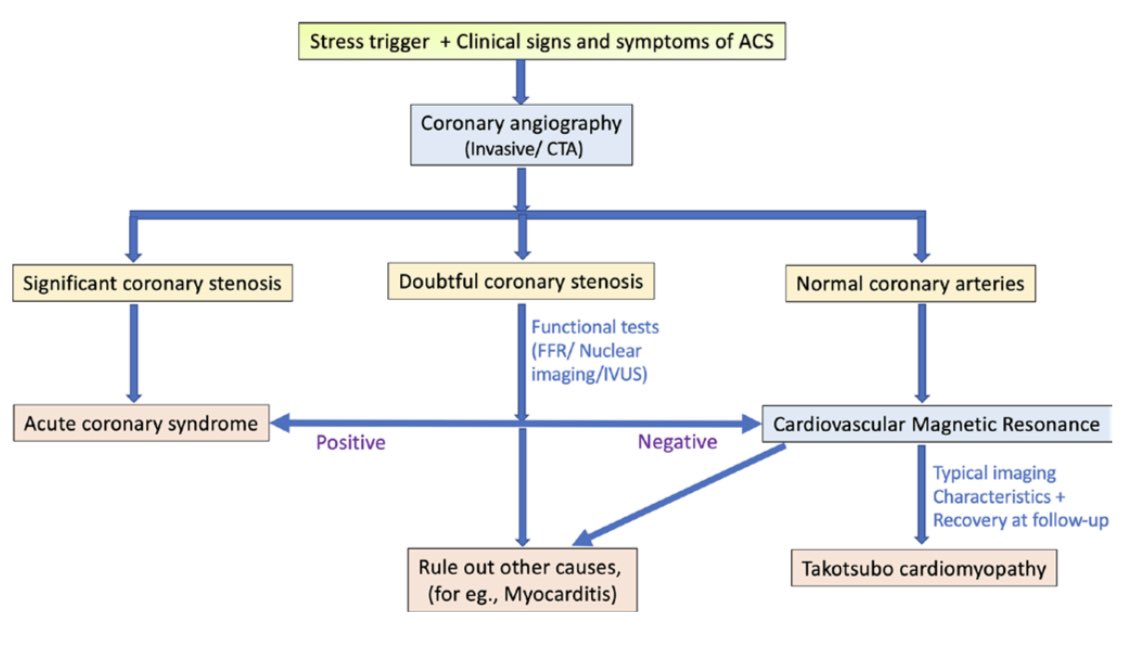

Role of #whyCMR in Takotsubo CM (TC):  reversible

reversible  transient LV dysfunction

transient LV dysfunction  most commonly basal hyperkinesis and mid-apical

most commonly basal hyperkinesis and mid-apical

LV ballooning and hypokinesia (a) other phenotypes may be present (b-d)

other phenotypes may be present (b-d)  diffuse edema/raised T2

diffuse edema/raised T2

https://www.birpublications.org/doi/abs/10.1259/bjr.20200514

reversible

reversible  transient LV dysfunction

transient LV dysfunction  most commonly basal hyperkinesis and mid-apical

most commonly basal hyperkinesis and mid-apicalLV ballooning and hypokinesia (a)

other phenotypes may be present (b-d)

other phenotypes may be present (b-d)  diffuse edema/raised T2

diffuse edema/raised T2 https://www.birpublications.org/doi/abs/10.1259/bjr.20200514